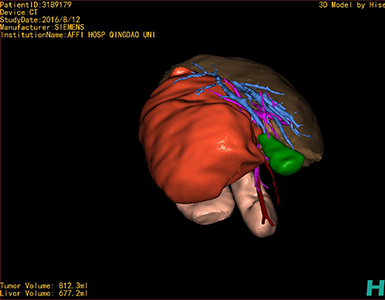

将0.625mm双源薄层CT资料的静脉期和动脉期Dicom格式文件导入海信CAS系统。

通过调节窗宽窗位调整CT序号,对肿瘤,肝实质,胆囊,下腔静脉,肿瘤,肝动脉、门静脉及肝静脉等进行三维重建;系统自动计算肿瘤体积和肝脏体积。

模拟手术操作,自动计算切除肿瘤体积。肝脏体积为660.9ml,肿瘤体积为812.3ml,肿瘤体积为肝脏体积的122.9%,通过比对3-4岁正常肝脏体积为522.63±121.24 ml,肿瘤所占比例较大,且包裹右侧肾脏、及腹腔大血管,手术无法完整切除肿物,不建议给予手术治疗。